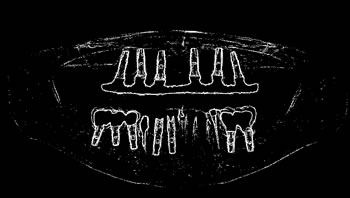

Figure 4: Annotation of the teeth.

Image annotation

The process of annotating the images of our proposed data set occurred in two parts. First, it was initiated by the upper jaw through the annotation of the third right upper molar and making the annotation of all the teeth of the upper arch to the third left upper molar. Then, the same process was performed on the lower jaw with all the teeth, and in the same direction as the upper jaw, from left to right, starting with the annotation of the third right lower molar, and annotating all teeth from the lower arch to the lower third molar. Figure 4 illustrates the tooth annotation process through a panoramic X-ray image of the data set.